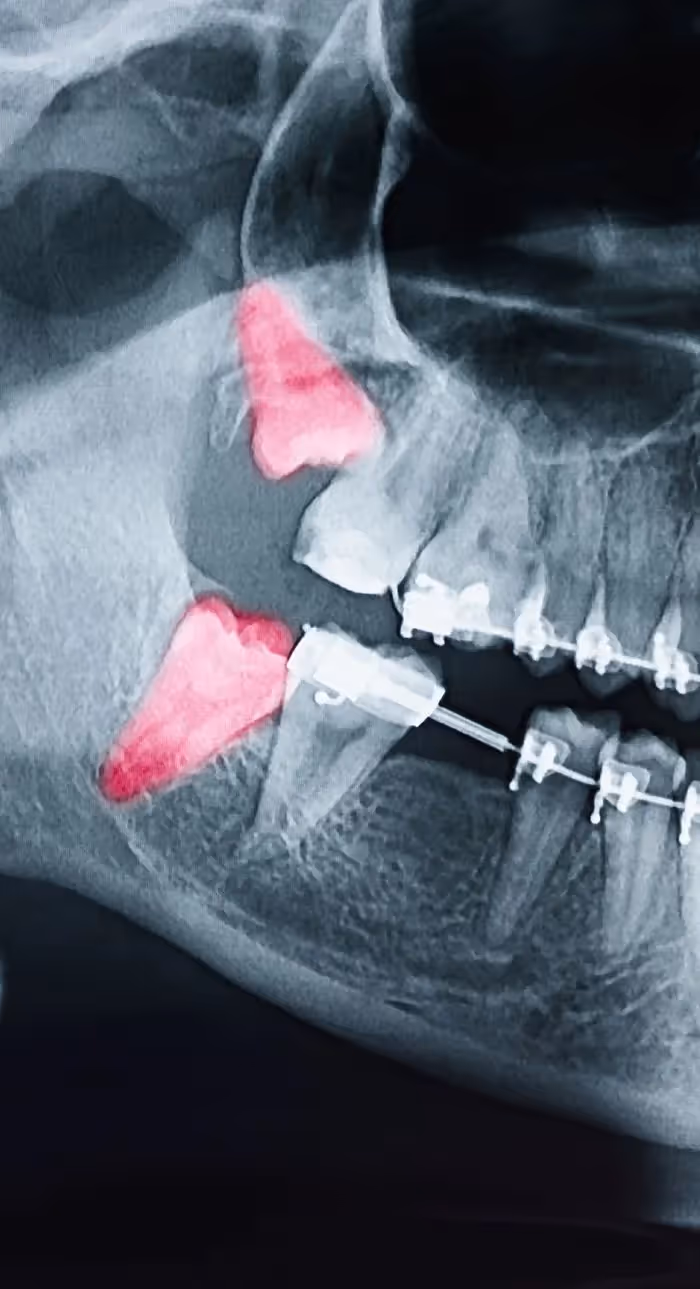

Impacted Wisdom Teeth Are No Match For Us

Impacted wisdom teeth can be particularly complex to remove. You can trust our team to remove your impacted wisdom teeth efficiently, without pain, and with minimal discomfort during your healing and aftercare.

With digital x-rays, we get high-resolution images of your teeth that allow us to make more accurate diagnoses. When you’re in pain or experiencing an emergency, we can see why the tooth is reacting and if an extraction is needed.